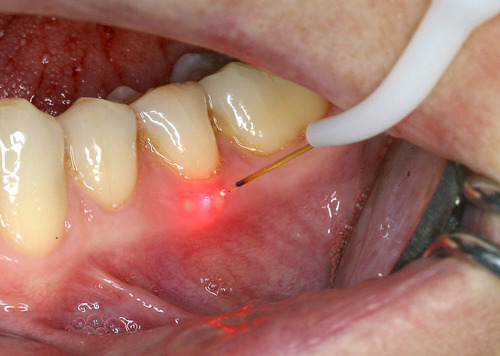

Par exemple, sur des aphtes douloureux (fig. 20) un rayonnement laser est rapproché progressivement jusqu’à une disparition quasi complète des sensibilités (fig. 21).

Fig. 21 Traitement avec un rayonnement laser pénétrant